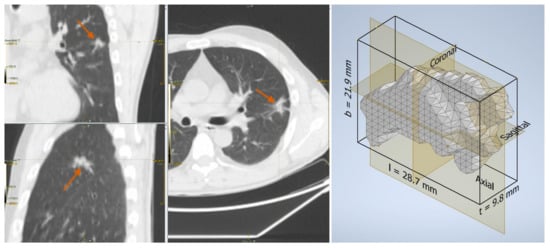

2.2. Lesion Delineation

2.3. Shape Features